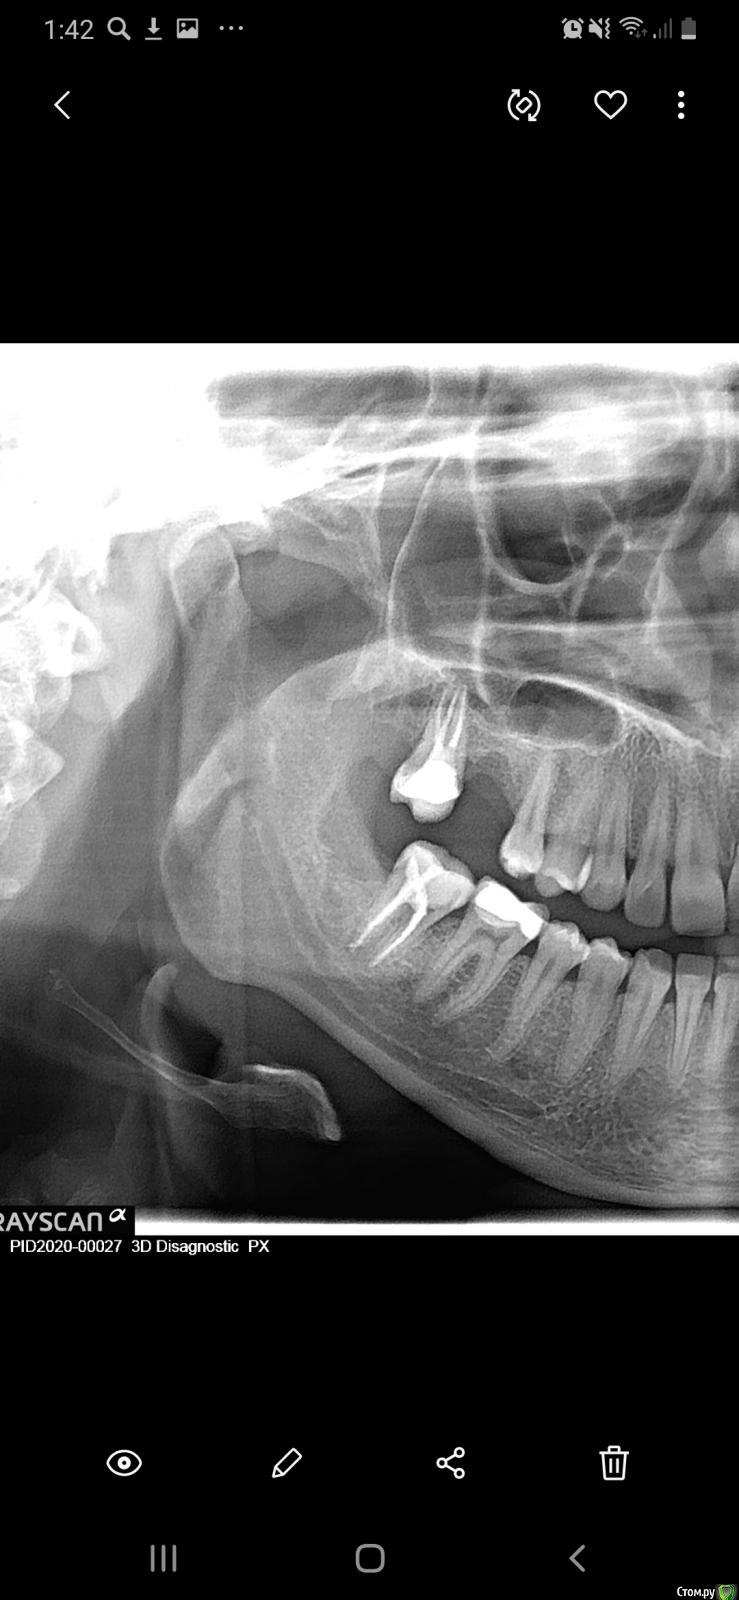

Kartohka Опубликовано 10 января, 2020 Автор Поделиться Опубликовано 10 января, 2020 Вот лучше качества Ссылка на комментарий

Kartohka Опубликовано 10 января, 2020 Поделиться Опубликовано 10 января, 2020 Добрый вечер)Уже месяц беспокоят боли в десне справа 7 нижнего зуба, болит в области десны при нажатии и при постукивании, чувство жжения и буд-то иголки вставляют под десну, плюс поясился дискомфорт между 4 и 5 зубом нижним, при открытии рта и зевании дискомфорт у 5 зуба, при соприкосновении с щекой, чувство что под десной инородный предмет, вырвали зуб номер 8 пару мпсяцев назад ,при этом подвывихнули челюсть Ссылка на комментарий